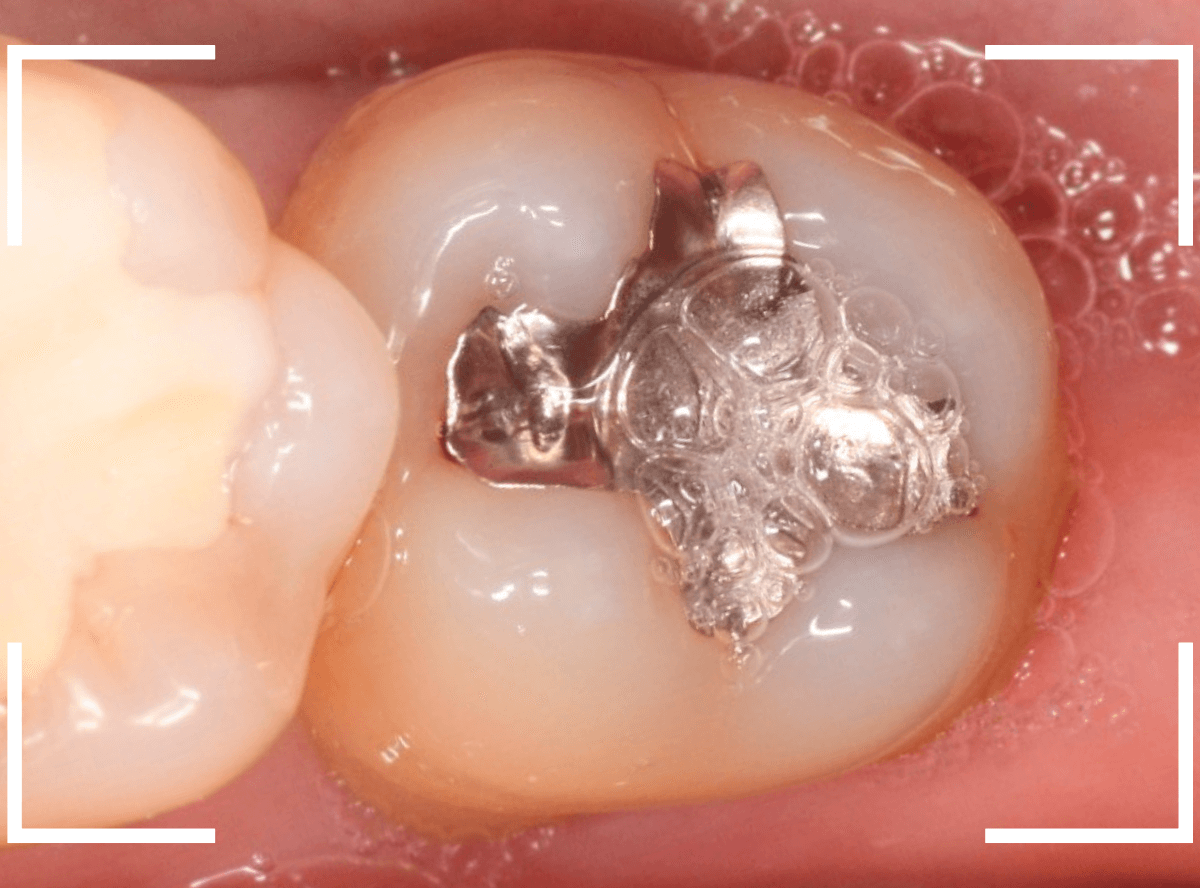

Case.10 劣化したメタルインレーの下の深い虫歯

レントゲンで大きな虫歯が見つかった方です。

古いメタル・インレーの中がぼやっと黒く透けて見えて「アヤシイ!」と思い、レントゲン写真で確認します。

他の歯の治療希望で来院された患者さんで、レントゲンで大きな虫歯が見つかった方です。

以前に虫歯を削って、レジンをつめる治療がしてあります。

表面を見る限り、特に問題はなさそうです。

メタル・インレーを外して確認します。

思った以上に虫歯は広そうです。

外したメタル・インレーの内側は真っ黒です。

慎重に全ての虫歯を除去したところです。

丸部は、神経の入り口が少し見えている状態で、かなり際どい虫歯でした。

しばらく経過観察後、特に症状もみられませんでしたので、問題なしと判断して最終修復に移ります。

最終的にメタル・インレーをsetしたところです。

メタル・インレーの欠点の一つに他の材料に比べてしみやすい、というのがあります。

今回は、歯の神経のすぐそばまでの際どい虫歯でしたので、メタル・インレーはしみやすいので、慎重に経過観察の必要があります。